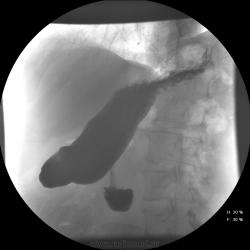

Насколько я понял, интересующий момент в постбульбарном отделе. Но ведь картина непостоянная. В вертикальном положении постбульбарный отдел (нисходящий) без проблем. Может быть перистальтическая волна?

Отвечу сам себе. Более внимательно рассмотрел все рентгенограммы (утром заскочил на сайт на 5 минут) - очень похоже на симптом обратной тройки (Фростберга), а стало быть объемный процесс головки панкреас.

Ответов конечно много,но: - кольцевидной панкреас у пациента нет (ни раз проводили кт - там хрон панкреатит,кисты, подозрение на образование , но это уже в течении 2 лет...) - рака ДПК, полипов, язвы нет - несколько раз проводилось ФГДС; - пролапс может и есть , но не в нем проблемы...;

почему выставил этот случай , так как видел и раньше такую картину в этом месте (нисходящая часть ДПК). В данном случае ФГДС, УЗИ дают образования в этой области, да и на р-скопии подобные находки... а могут ли быть в этом месте увеличенные л.узлы?

... в заключениях УЗИ и ФГДС фигурирует луковица ДПК, при Rg-логическом исследовании - нисходящая часть ДПК.

Импонирует псевдотуморозный панкреатит с кистами в головке железы, циркулярно охватывающей/ перегибающейся через нисходящую ветвь ДПК (оттеснение (на одном снимке - правильный рельеф слизистой) по (передне-)латеральной стенке кишки), НО... автор уверяет, что кольцевидной железы у больного нет, а есть кисты/образование. Вот локализация этого "образования" по КТ (в т.ч. по отношению к колену ДПК и ответит на вопросы - "что это и откуда?"